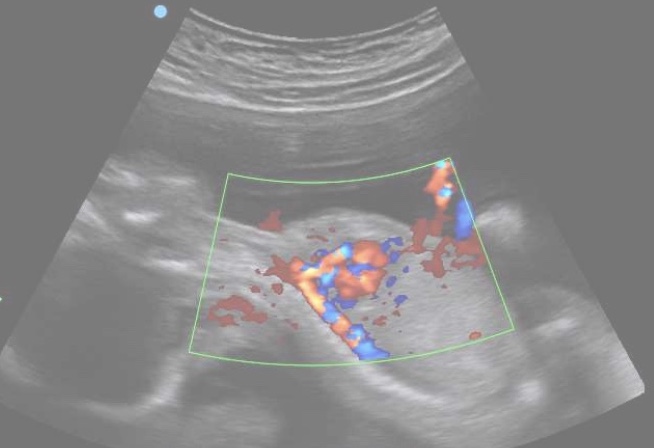

He grasped at his cord, it was still there! ‘Phew!’

‘Pops is coming Nick’ the great mother whispered gently.

‘He will follow you in his own natural time.’

Suddenly Pops came out and was next to Nick.

The great mother embraced Nick with all her love as the very last pulse of blood pumped from Pops cord into Nick.